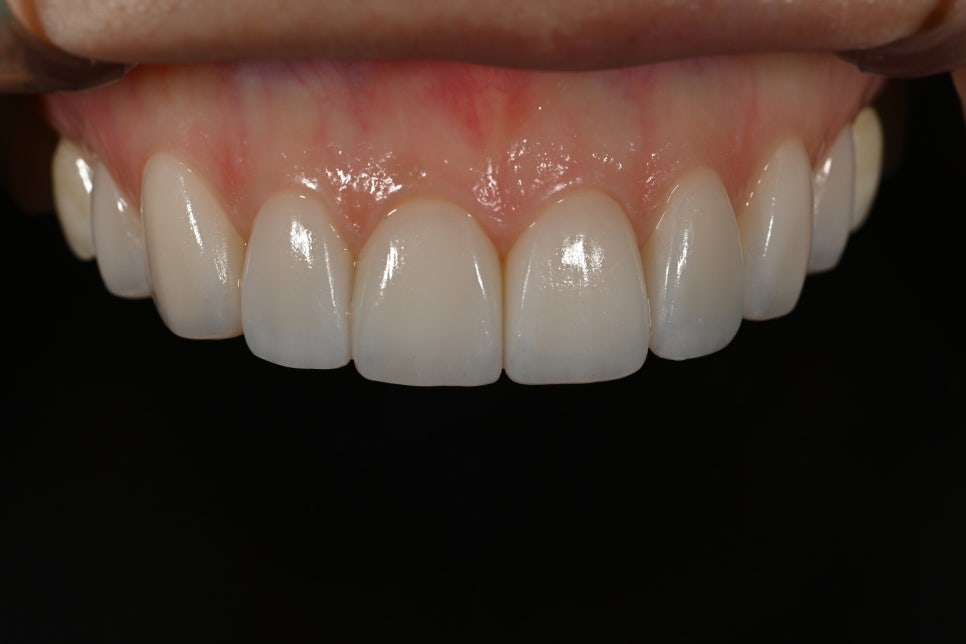

Changes after treatment

<BEFORE>

<AFTER>

After treatment, the patient experienced

a natural smile

a softer change in impression

greater satisfaction in photos

In particular, there were many comments like

"I can't tell that they had laminates"

"It just feels like they became prettier."

This is exactly the result of

Obzero Pure Laminates.